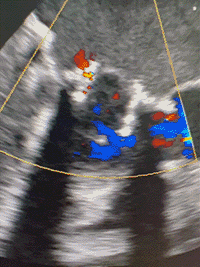

术中,术者可以通过观察定位件跳动的形态判断瓣膜位置,同时可以清晰感觉到力的反馈。经过几次调试,定位件稳稳锚定原瓣架,可看到三个定位件随着心脏搏动而自然摆动。确定好位置后释放瓣膜,锁丝脱钩,瓣膜与植入器完全分离。观察瓣周漏与瓣膜形态,经食管超声心动图显示瓣膜位置合适,形态良好,无瓣周漏和反流。